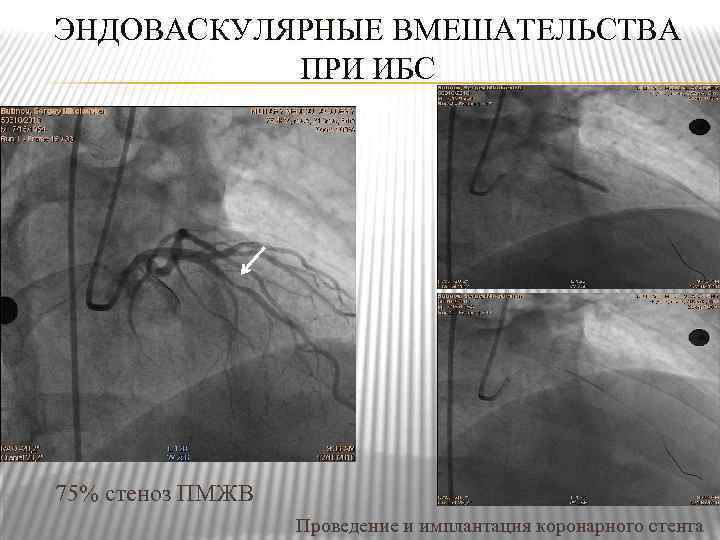

ЭНДОВАСКУЛЯРНЫЕ ВМЕШАТЕЛЬСТВА ПРИ ИБС 75% стеноз ПМЖВ Проведение и имплантация коронарного стента

ЭНДОВАСКУЛЯРНЫЕ ВМЕШАТЕЛЬСТВА ПРИ ИБС 75% стеноз ПМЖВ Проведение и имплантация коронарного стента